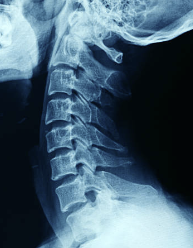

우리 목 뒤쪽엔 여러 신경들이 머리로 지나가게 되어 있고, 이 부분에 압박이 느껴지면

뒷골이 땡기는 듯한 느낌을 받는다고 합니다.

디스큰 아니지만 일자목 역시 뒷목 땡김에 큰 영향을 끼칩니다.

사람의 목은 C자 커브가 된 상태가 건강한 상태인데,

1자의 상태가 되면 디스크에 무리가 가고

목과 어깨에 무리가 가기 때문에 뒷골 당김 현상이 생길 수 있습니다.